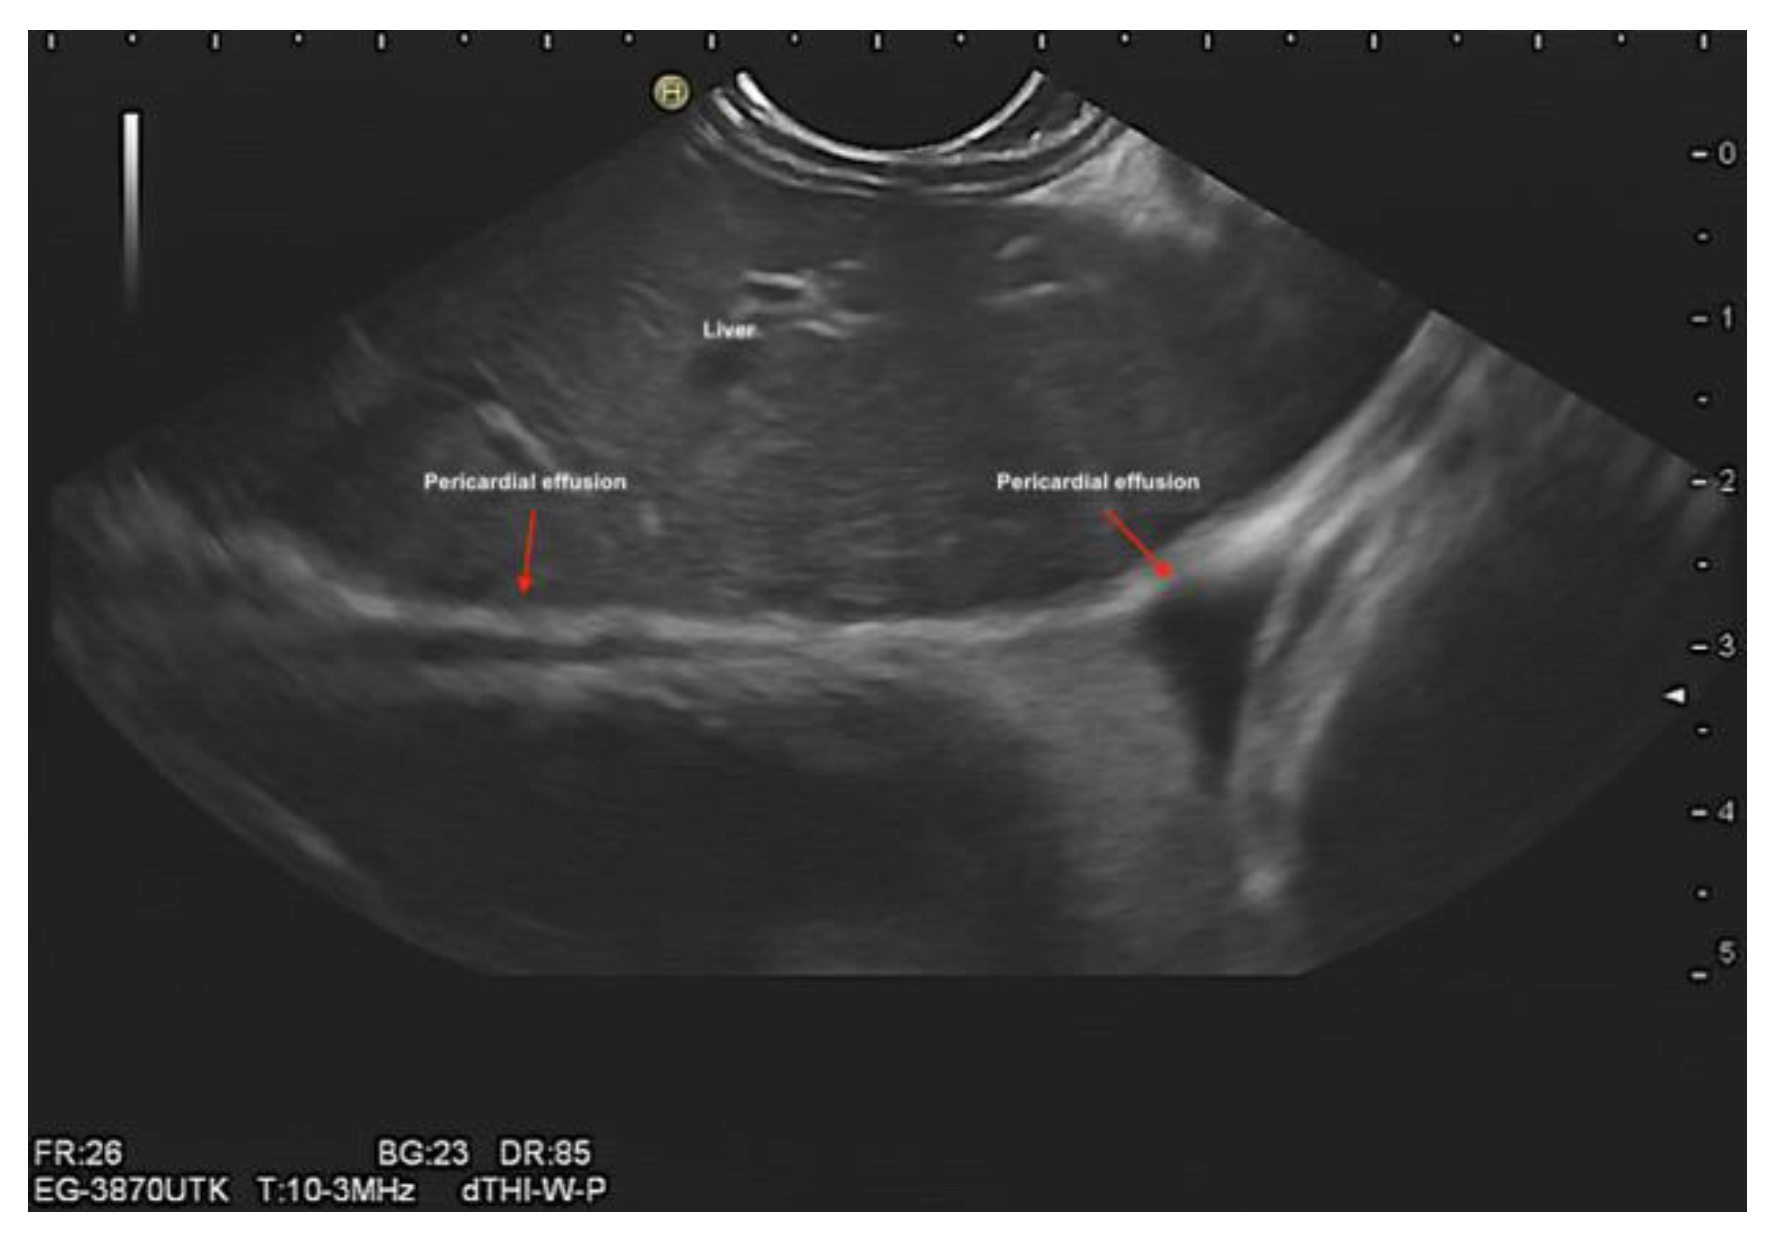

Evaluation of pericardial effusion (Figure 9).

Figure 9. Endosonographic ultrasound demonstrated a minimal pericardial effusion.